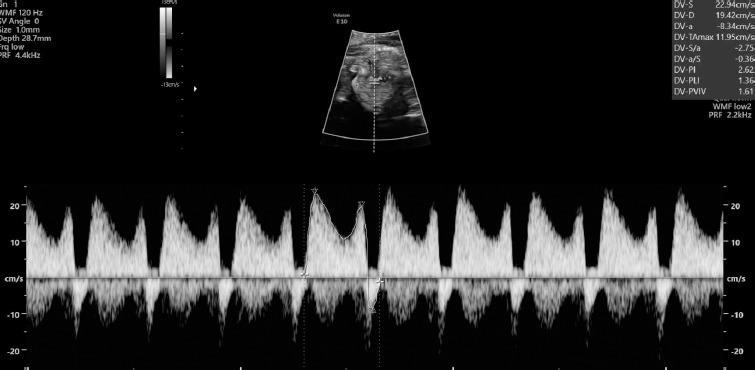

A thirty-three-year-old pregnant woman in her second pregnancy (the first pregnancy was unsuccessful – miscarriage at week 8 of pregnancy), visited a gynecologist for a routine check-up at week 12 of pregnancy, during which developmental disorders were found in the anterior chest cavity and abdominal walls. The woman was healthy, denied having chronic diseases, and was taking folic acid and vitamin preparations for pregnant women. The patient also denied the existence of any infections at an early stage of pregnancy. The woman was referred to the Laboratory of Prenatal Research, where, during prenatal ultrasound examination, the fetus was diagnosed with a complex defect of the skin and division of the body’s cavities in the form of pentalogy of Cantrell. The fetus was diagnosed with umbilical cord omphalocele (Figure 1), diaphragmatic hernia with diaphragmatic defect, sternal defect, ectopic heart and pericardial defect (Figures 2-3).

Moreover, the fetal heart seemed to possess four cavities, two slightly asymmetrical inflows of the ventricles and the origins of two vessels in abnormal relationships were visualized (Figures 4-5).

The swelling of the entire fetus was visualized – NT 5 mm (Figure 6) and reverse flow in the ductus venosus (Figure 7).